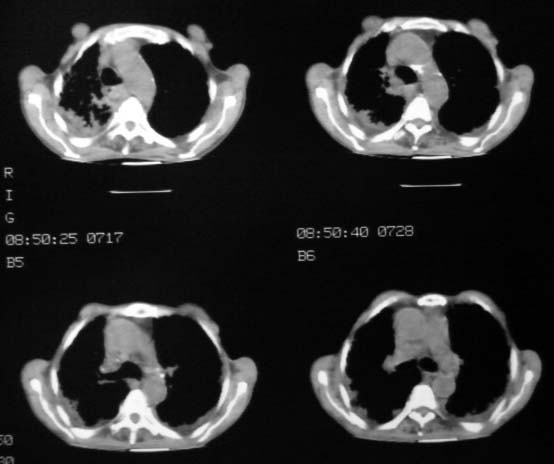

男,85岁,发热2月, 血常规:hgb99g/l.rbc2.55×1012/l.wbc3.8×109/l.n78.2%  l20.7% m1.1%.  hct26.3% .血沉20mm/hg.痰检结核杆菌阴性。ddp阳性。痰少粘稠色白。无咳血。

1.右上肺陈旧性肺结核灶;

2.左上肺、双下肺及右中叶肺炎(左上肺肺炎治疗后好转)

右上肺陈旧性肺结核灶,双肺感染灶〔大部份纤维化〕,肺气肿.

双肺继发型肺结核,肺纤维化,肺气肿,胸膜肥厚黏连。